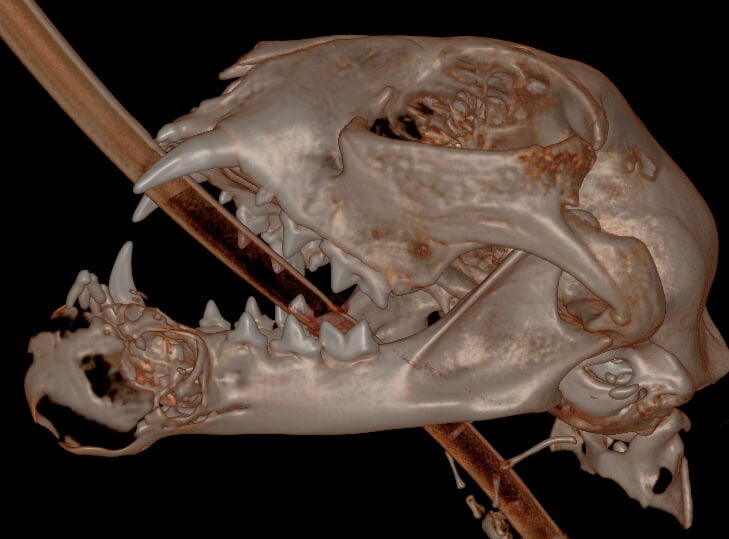

Removing or shortening the mandibles can be helpful. Most patients are more comfortable and can have a relatively cosmetic outcome. Sometimes the mandibles are removed due to fractures that cannot be repaired. This case was removed due to an oral tumor.

Bilateral rostral mandibulectomy to excise an oral mass that is suspected to be benign (not spreading) but locally invasive. Oral surgical removal of unerupted/impacted lower left canine tooth occupying the majority of the left mandible.

Bilateral rostral mandibulectomy was performed to excise the mass with submission to the oral pathologist (SOPA, www.sopforanimals.com). The mass was confirmed to be a FIOT (feline inductive odontogenic tumor) which does not spread to other organs but expands and is locally invasive requiring oral surgical excision. Margin mass excision was performed by removing the growth enblock extending to the middle of the left mandible and including the right canine (prevents impact with palate in the case of secondary mandibular drift).

Chin and lip tissues were preserved where possible as well as the sublingual salivary caruncles. The tongue side of the left mandible was partially preserved to allow for the remaining mandible segments to meet which will improve the long term occlusion/chewing capability. It is likely the patient will just be a normal cat with a short lower jaw length. The remaining lower cheek teeth were blunted to prevent trauma should one or both mandibles drift inward.

Histopathology confirms the diagnosis of feline inductive odontogenic tumor, which is histologically indistinguishable from an ameloblastic fibroma. FIOT/ameloblastic fibroma is a benign tumor of odontogenic epithelium that includes induced odontogenic mesenchyme. Because this lesion occurs almost exclusively in young animals, there is some possibility that is a hamartoma (i.e. proliferative developmental tumor) rather than a true neoplasm.

Complete excision is expected to be curative. In this case, the margin on the left is histologically “dirty” although this may not truly represent the biological margin. Overall, margins are promising since the neoplasm does not infiltrate soft tissues and the mass extends just to the margin where additional debridement of left mandibular bone may have removed small amounts of remaining neoplastic tissue. Close monitoring is advised.